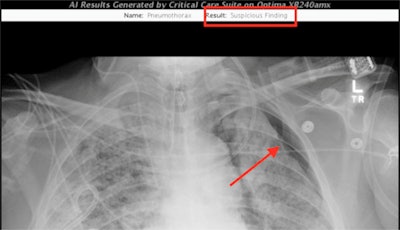

An AI algorithm developed by UCSF researchers identified a pneumothorax in a recent intensive care unit patient. The red annotations were added manually to highlight the finding. Image courtesy of Dr. John Mongan, PhD, and UCSF.Another algorithm measures the position of the endotracheal tube. It was created by Valentina Pedoia, PhD, and Sharmila Majumdar, PhD, with contributions from Dr. Thienkhai Vu, PhD, and Dr. Rutwik Shah, according to UCSF.